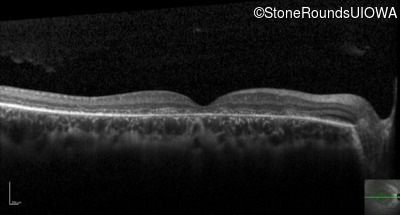

Optical Coherence Tomography - Right - 20/200 -3

Exemplar / OCT Stack

OCT Stack